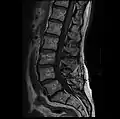

MRI lumbar spine with degeneration, post-hemilaminectomy L4-5 (sagittal FAST STIR)- MRI lumbar spine post-hemilaminectomy (sagittal T2 FRFSE)